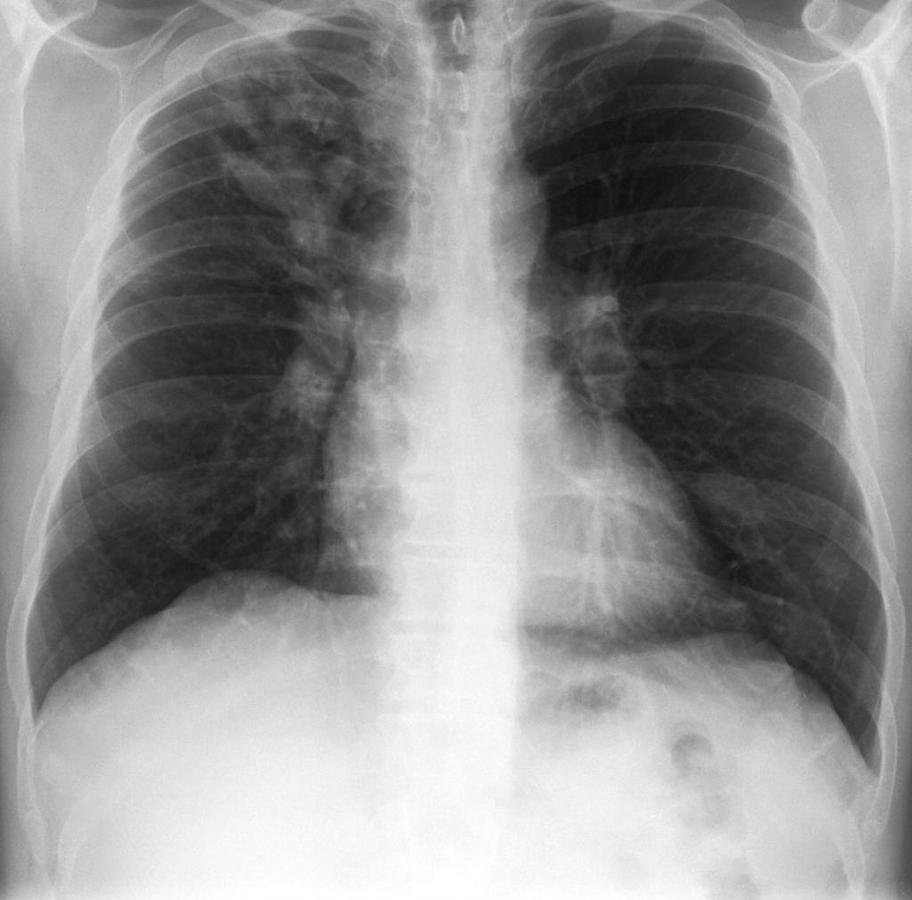

Chest Xray

X-Ray

If early, there may be no signs of infection on CXR

Classically, there is consolidation and mucoid impaction

Some notable signs include

Finger-in-glove opacities

"Toothpaste shadows"